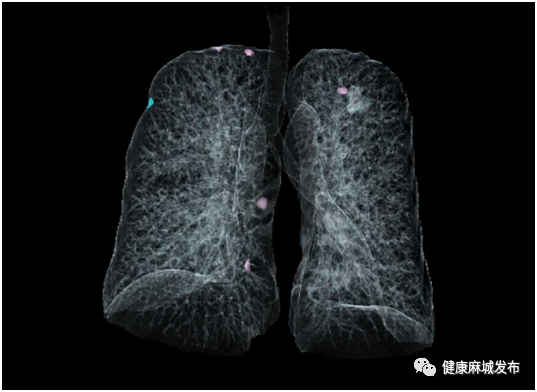

肺结节评估:智能自动筛查与定量分析微小结节,支持多次扫描随访分析与一键式结构化报告智能生成,大幅提升工作效率。